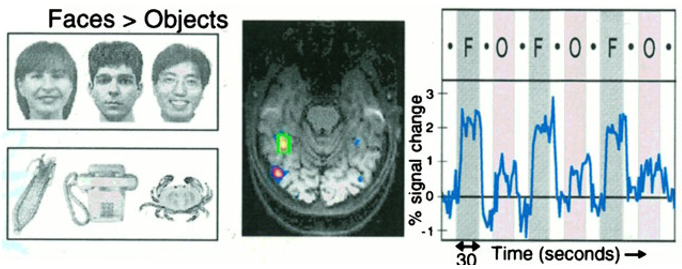

Prof Nancy Kanwisher (Ref.1) and her team used functional magnetic resonance imaging (fMRI; Ref.2) to scan brain activity as human subjects viewed faces and objects. Their work led to the identification of a small region of the neocortex, now known as the fusiform face area (FFA), which responds selectively to faces (Figure 1; Ref.3). This discovery not only confirmed the existence of a face-specific recognition system in the human brain but also introduced new techniques for identifying specialised brain regions. Prof Kanwisher’s methods for localising functional areas have since become widely used across neuroscience, extending beyond face recognition to other cognitive domains.

Figure 1. The fusiform face area (FFA), as identified by fMRI, showing stronger activation in response to faces compared to objects. Adapted from Ref. 3.